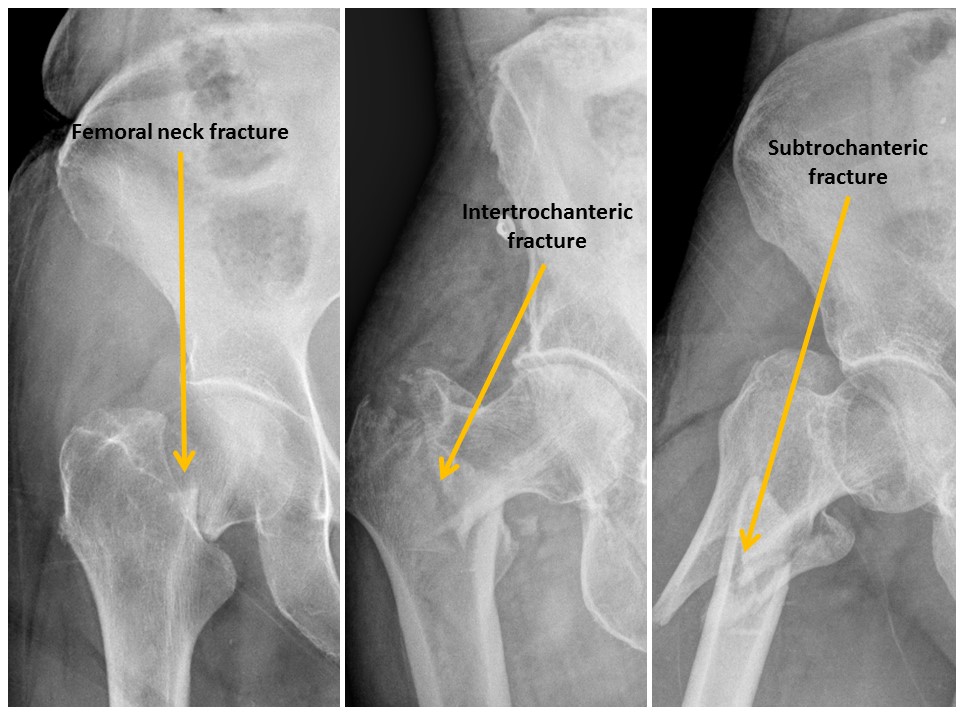

There are fractures of the femoral neck, intertrochanteric region, or subtrochanteric region. [Yes/No]